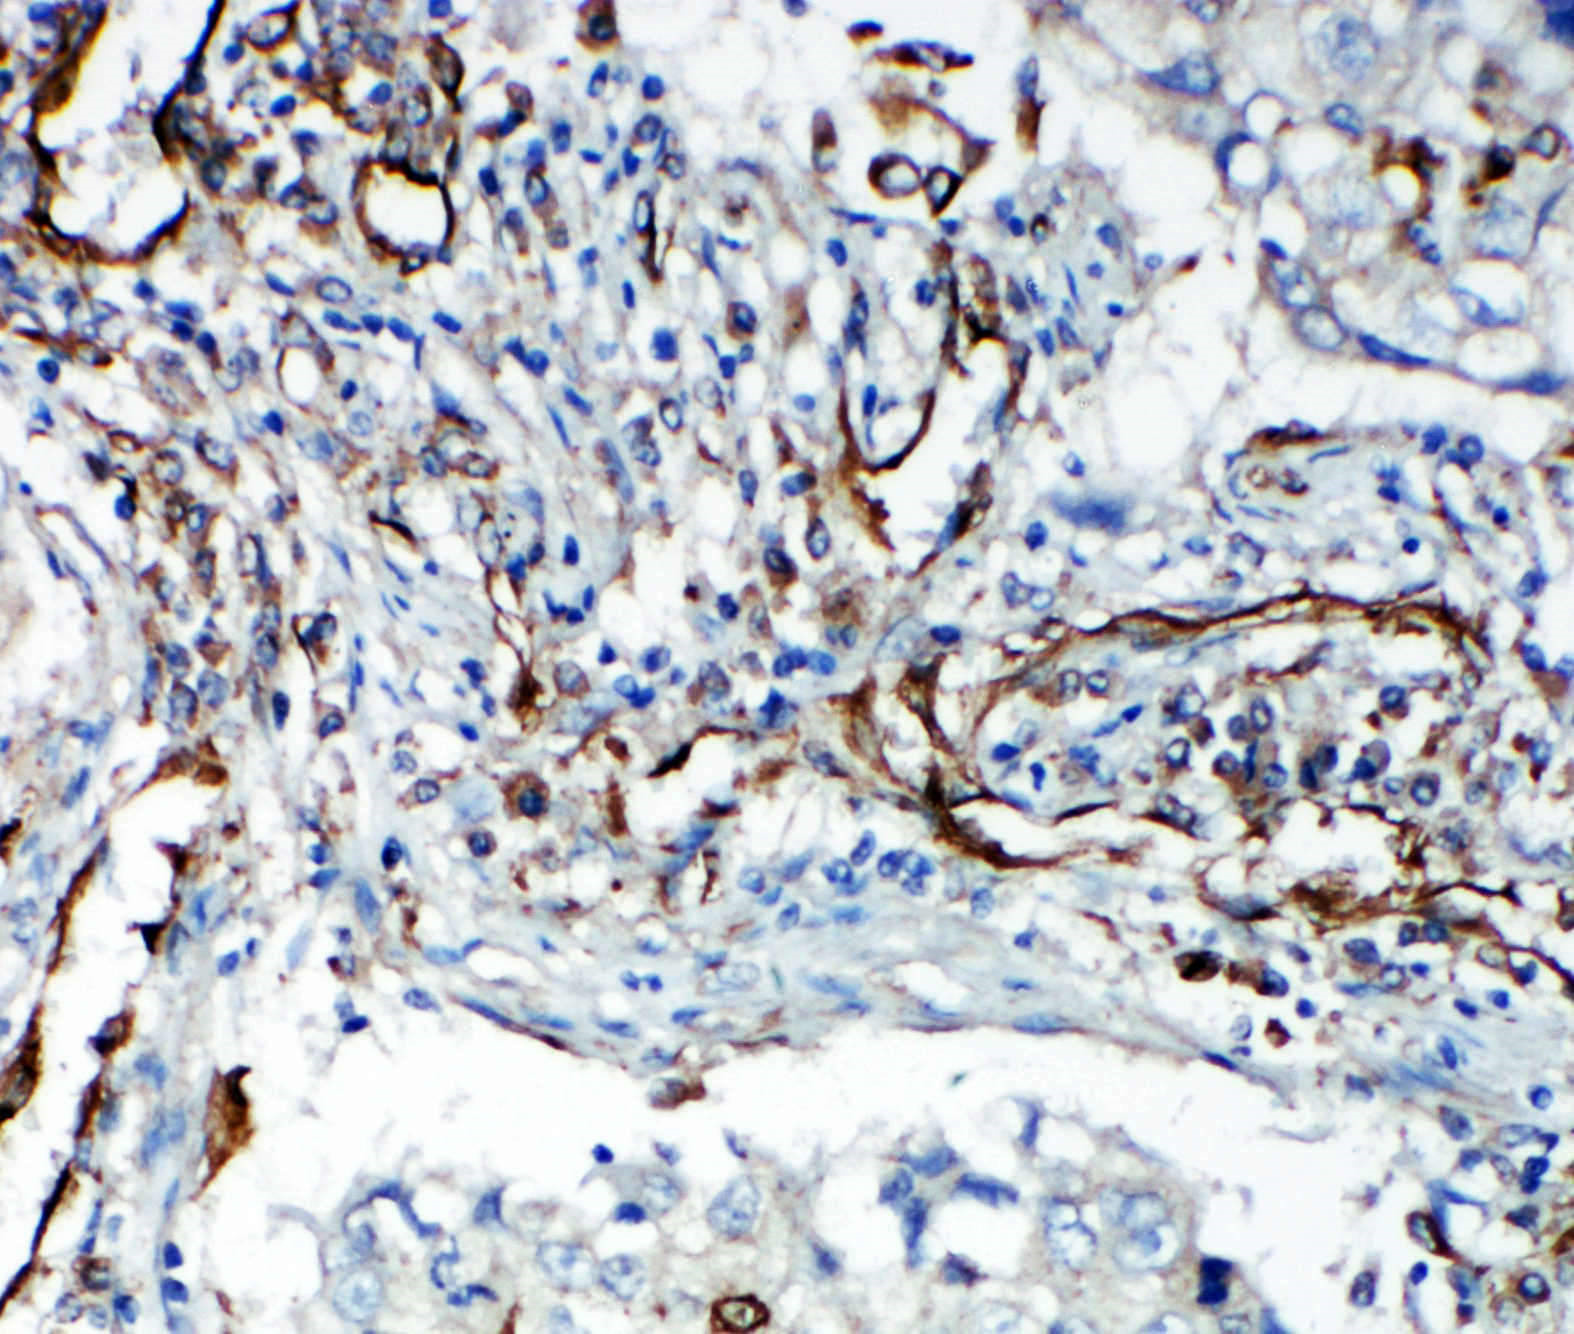

IHC analysis of VEGFR2/KDR using anti-VEGFR2/KDR antibody (BA0472).

VEGFR2/KDR was detected in a paraffin-embedded section of human lung cancer tissue. The tissue section was incubated with rabbit anti-VEGFR2/KDR Antibody (BA0472) at a dilution of 1:200 and developed using HRP Conjugated Rabbit IgG Super Vision Assay Kit (Catalog # SV0002) with DAB (Catalog # AR1027) as the chromogen.